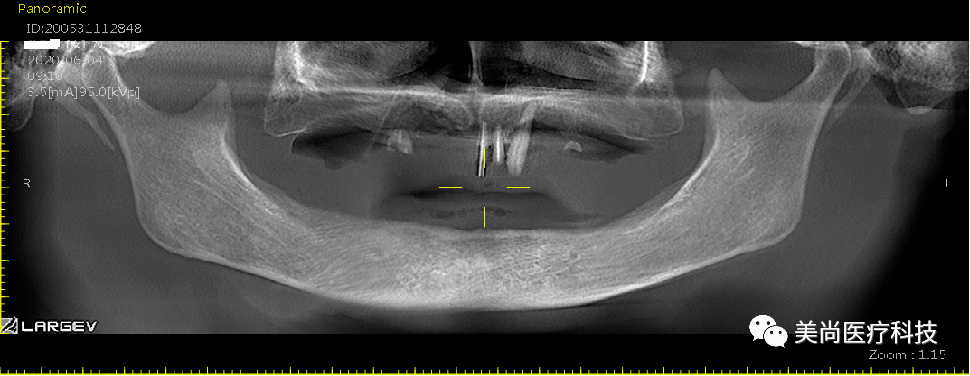

上颌可见烤瓷连桥修复Ⅲ°松动,牙龈微红肿;

下颌无牙颌附着龈狭窄仅1mm,牙槽嵴呈刀刃状;

32、42可用骨宽度6mm,可用骨高度10mm;

34、44可用骨宽度6mm,可用骨高度11.5mm。

制作导板,导板引导下植入种植体

导板下植入植体:

在32、42处植入3.5*10mm植体各一颗,植入扭矩约35n.cm;

在34、44处植入4.0*11.5mm植体各一颗,植入扭矩约40n.cm。